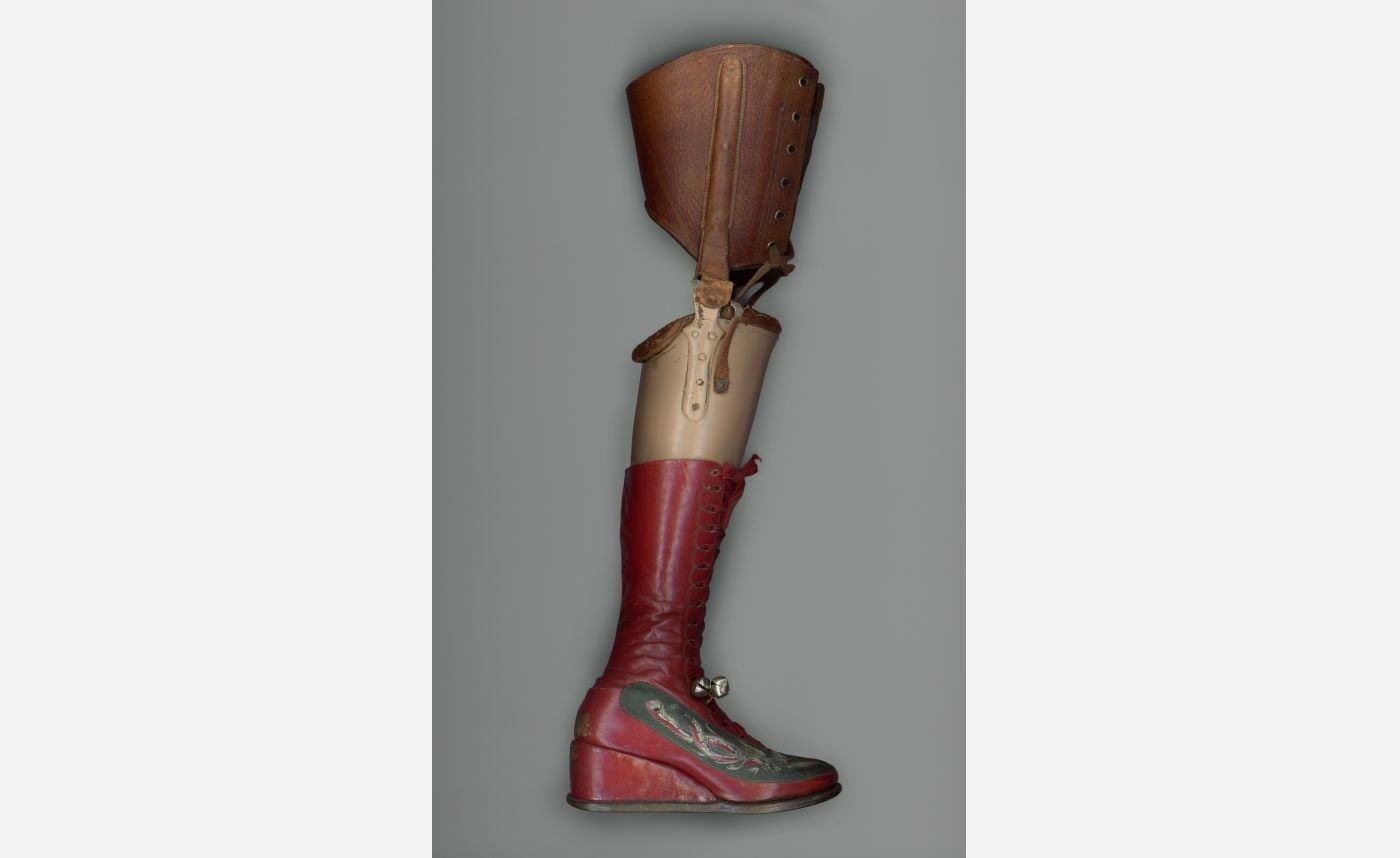

Her Lower Limbs

At the age of 6, Frida Kahlo contracted polio virus, resulting in her right leg being shorter and thinner. This physical disability was further complicated by the streetcar accident, in 1925, that caused 11 fractures in her right foot. As a result, Frida lived with chronic pain in her lower limbs, often having to be treated for foot ulcers that were largely due to vascular insufficiency. Eventually doctors amputated five phalanges, or bones in Frida’s right foot as well as a smaller bone, the sesamoid.

The last major recorded surgery Frida Kahlo underwent was an amputation of her right leg, on 11 August 1953—less than a year before her passing. The amputation was performed due to Frida having been diagnosed with gangrene—a medical condition that involves the death of body tissue due to a lack of blood flow or a serious bacterial infection.

The objects photographed here were used by Frida to enable her to go about her everyday life—considering her damaged body. She often sat in her wheelchair too weak to walk, she wore corsets to support her weak spine and her prosthetic leg took the place of her amputated right leg.

Katerina Jebb, Prosthetic Leg, 2022, digital image printed on paper. Courtesy of the artist.

Katerina Jebb, Prosthetic Leg, 2022, digital image printed on paper. Courtesy of the artist. -